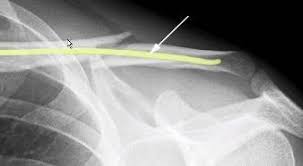

Hier muss dann bei Beschwerden eine aufwendige Korrekturoperation erfolgen. Sogar inklusive des eingesetztem Draht. In manchen Fällen macht der Schlüsselbeinbruch aber eine Operation notwendig zum Beispiel wenn gleichzeitig die unter dem Schlüsselbein liegenden Blutgefäße oder Nerven verletzt oder die Knochenbruchstücke stark verschoben sind.

Nach einer Schlüsselbein OP wurde operativ ein Draht eingesetzt. Die Bewegungsfreiheit ist bei mir nach 8 Tagen wieder fast komplett hergestellt.